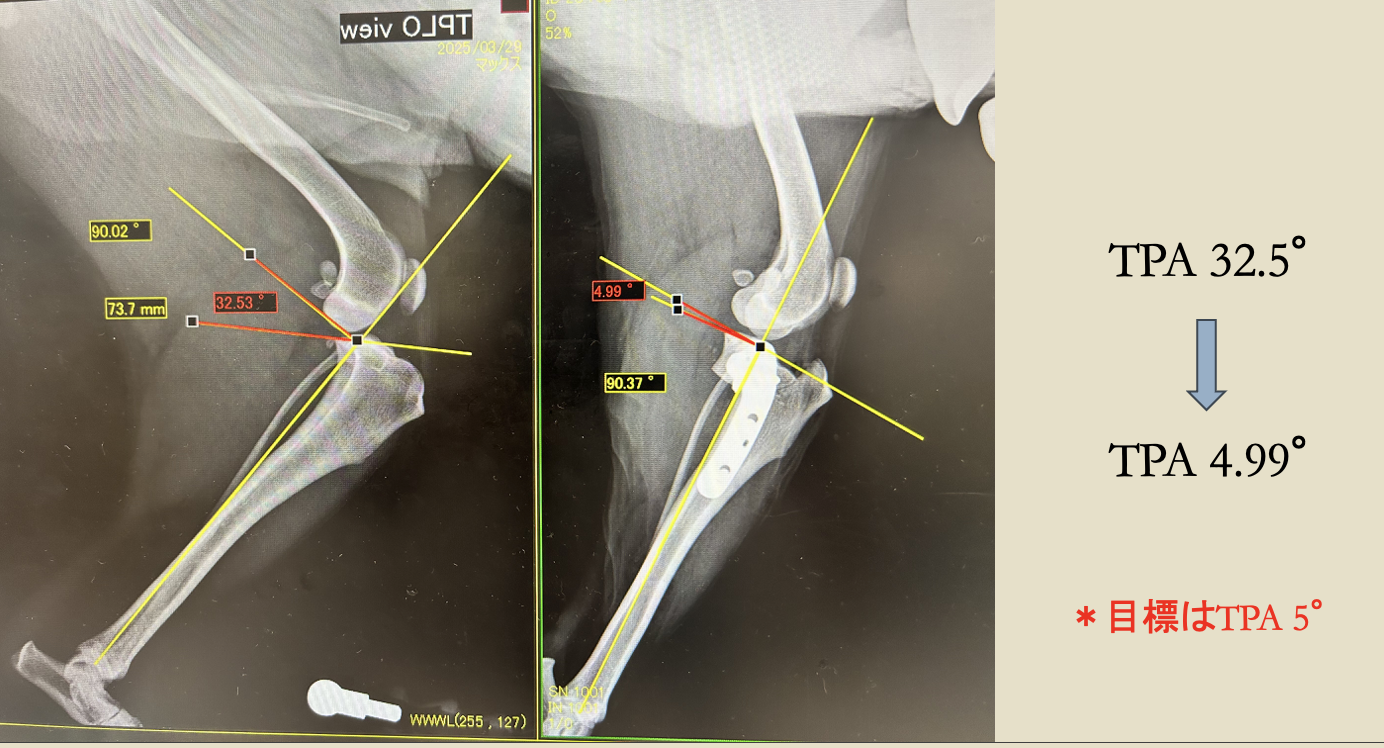

触診、レントゲン検査より、脛骨の前方変移、TPA(Tibial Plateau Angle 脛骨高平部の角度)32°が認められた

TPLO(脛骨高平部水平化骨切り術)

before

after